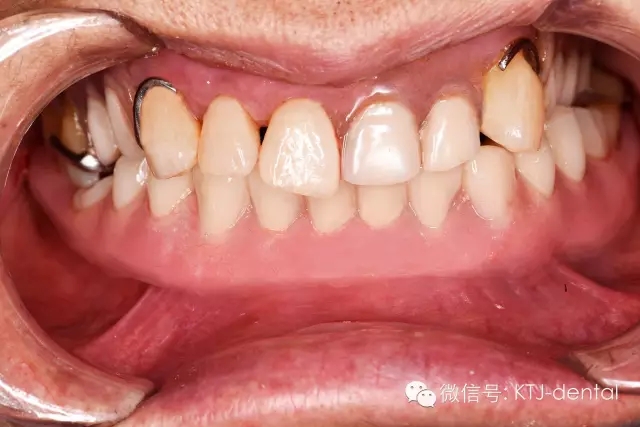

4即刻種植即刻修復的最終,全口正面照

本病案小結(jié):使用預成種植套筒冠基臺行無牙合即刻負重手術(shù)操作簡單,效果可靠,臨床應用方便快捷。但種植體的平行度是保證此修復方式成功實施的關鍵。本病例的CAD CAM手術(shù)導板在應用過程中發(fā)揮以下作用:嚴格控制種植體的平行度,避免損傷下牙槽神經(jīng)及頦神經(jīng)(無須翻瓣暴露神經(jīng)),根據(jù)種植體植入深度預選適當?shù)幕_,根據(jù)術(shù)前打印模型預先調(diào)磨即刻負重義齒。CAD CAM手術(shù)導板的應用使得手術(shù)操作有更強的預期性。在應用技巧方面,預先保留不影響植入位點的牙齒,獲得更為精確的牙支持式的手術(shù)導板,減少了手術(shù)誤差。半程導板配套的器械盒應該合理地與相應種植系統(tǒng)外科器械配合使用,并根據(jù)骨的質(zhì)地采用相應的預備方式,使得植入位點精確,并獲得良好的初期穩(wěn)定性完成下一步的即刻負重治療。